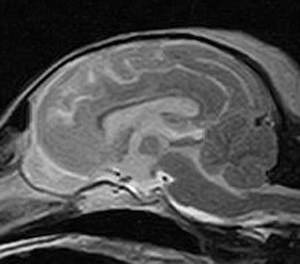

けいれん発作が出るワンちゃんが来院されました。MRI検査では脳に構造上の異常を認めず、特発性てんかんとの診断でお薬での治療となりました。発作は現在のところ、お薬で良好にコントロールされています。